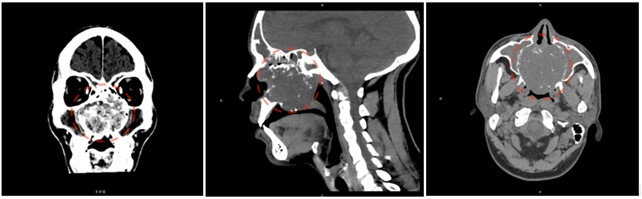

L’imaging effettuato nei mesi successivi e le biopsie di controllo, eseguite a un anno dalla fine della terapia, evidenziano l’assenza di recidiva della patologia oncologica, come si evince anche dall’immagine radiologica. Attualmente il paziente riferisce una buona respirazione nasale e una normale ripresa della sua vita quotidiana senza lamentare peggioramenti della propria qualità di vita.